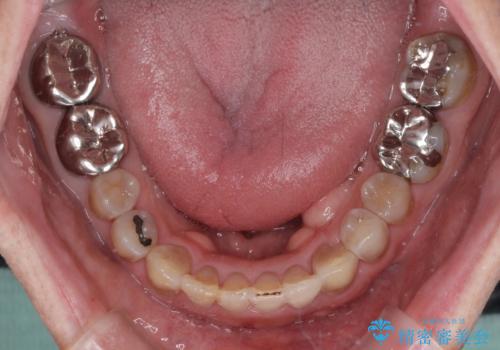

上顎の狭窄歯列 インビザラインによる拡大矯正

- 前歯の叢生と臼歯のクロスバイトを気にして来院された患者様です。

急速拡大装置による上顎の側方拡大を行い、その後はインビザラインより歯列を改善することとしました。

20代後半以降の男性は上顎骨の側方拡大処置の成功率が低く、今回も骨を拡大することができませんでした。

しかしながら、歯列を側方に拡大することができ、その後はインビザラインにて叢生を解消することができました。